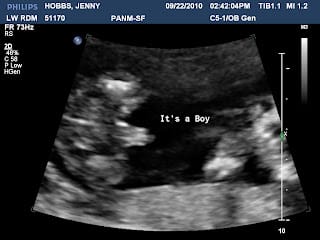

This picture shows clearly that he's a boy; that is not a finger.